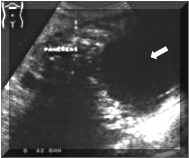

Sonographical

Findings:

Sonographically,

pseudocysts

are

well

defined

and

have

variable

internal

echogenicity.

hyperechogenicity

suggests

hemorrhage.

may

be

septated

or

contain

debris.

A

pseudocyst

confidently

diagnosed

when

persistent

fluid

collection

is

detected

in

the

clinical

setting

of

pancreatitis.

There

often

mass

effect

on

adjacent

bowel

loops

solid

viscera,

occasionally

definable

fibrous

pseudocapsule

(Pictures

1

2).